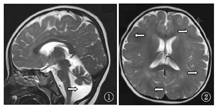

患儿,女,3岁,因"眼睑水肿20 d,稀便1 d"入院。患儿入院前20 d无明显诱因出现晨起双眼睑水肿,家长未予重视,无特殊治疗。入院前13 d,患儿双眼睑水肿加剧,伴腹部膨隆,就诊于当地医院,查尿常规+++,总胆固醇17.75 mmol/L,考虑肾病综合征,予口服泼尼松2 mg/kg,实际给予27.5 mg/d;入院前1 d出现发热,体温最高38.1 ℃,伴黄色稀水样便,水肿无明显改善,并出现尿量减少,小便2次/d,遂就诊于首都医科大学附属北京儿童医院肾内科。发育状况:患儿4个月抬头,8个月会坐,1岁6个月可扶走,3岁不会说话,仍需扶走。查体:血压100/50 mmHg(1 mmHg=0.133 kPa),头围46 cm,特殊面容(发际低,鼻梁宽扁,眼裂小,上唇长,颈短),行走不稳,眼睑及面部轻度水肿,咽充血,扁桃体Ⅰ度肿大,双肺呼吸音粗,未闻及啰音,心脏查体未及异常,腹膨隆,腹壁轻度水肿,腹围53 cm,移动性浊音可疑阳性,余腹部查体未及异常,脑膜刺激征及病理征阴性,双下肢轻度水肿。尿常规:蛋白+++,潜血++,镜检红细胞2~4个/高倍视野(HP),镜检管型1~2个/HP;血常规:白细胞21.4×109/L,分类中性粒细胞78%,血红蛋白150 g/L,血小板441×109/L;大便常规:黄色稀便,白细胞2个/HP,轮状病毒阳性。入院生化检查:总蛋白34.0 g/L,白蛋白11.9 g/L,胆固醇15.87 mmol/L,血肌酐、尿素氮正常,24 h尿蛋白定量155.75 mg/kg。入院前行头颅MRI:弥散性巨脑回畸形并白质发育不良(图1),小脑发育不良并后颅窝脑脊液增多(图2),符合Dandy-Walker变异型。染色体核型分析为46,XX;无其他异常。Gesell儿童智力发育诊断表:适应能力和精细动作能力轻度低下,大运动能力、语言能力和个人社交能力中度低下。结合病史及辅助检查结果诊断为肾病综合征(肾炎型);轮状病毒性肠炎;精神发育迟缓;Dandy-Walker综合征。予抗感染、对症止泻等治疗后,腹泻好转。继续足量泼尼松(2 mg/kg)口服,病情好转后带药出院。足量激素口服8周,期间间断给予甲泼尼龙冲击治疗3次,足量激素口服第4周起加用环孢素(3 mg/kg)口服,2周后调整剂量为5 mg/kg,多次复查尿常规提示尿蛋白+++,再次收住院行肾脏穿刺检查,结果:可见34个肾小球,其中1个球性硬化,余肾小球系膜细胞和基质轻度弥散增生,局灶、节段性中重度增生,其中14个节段性硬化伴灶状足细胞增生、肥大;肾小管上皮空泡及颗粒变性,灶状萎缩,肾间质灶状淋巴、单核细胞浸润,伴纤维化,小动脉无明显病变。免疫荧光:IgM(+),补体1q(±),IgA、IgG、补体C3、补体C4、Fib均阴性。电镜:肾小球系膜细胞和基质轻度增生,系膜区可见块状电子致密物沉积,基底膜未见病变,上皮足突可见融合,符合局灶节段性肾小球硬化症(NOS型)。

MRI shows pachygyria malformation

MRI shows cerebellar hypoplasia and cystic dilatation of the fourth ventricle

、精神发育迟缓、下肢/四肢轻瘫及运动发育落后于同龄儿。肾脏病理以NSO型表现居多,也可表现为弥散性系膜硬化、微小病变及系膜溶解[2,3,4],因此多数病例对于激素耐药并最终发展为肾衰竭。本例患儿为肾病综合征(肾炎型),伴精神发育迟缓、特殊面容及小头畸形,MRI提示存在巨脑回畸形,小脑发育不良及脑积水,符合Galloway-Mowat综合征诊断。

Dandy-Walke综合征是一种以第四脑室和小脑发育障碍为特征的少见的中枢神经系统发育畸形,通常不伴有其他系统受累表现,目前其病因尚不明确,可能与感染、遗传或代谢等因素有关。1914年由Dandy和Blackfan首先报道,其发生率为1/25 000~1/30 000妊娠,占婴幼儿脑积水的3.5%。临床可分为典型和变异型2类,后者相对前者临床表现轻,预后相对较好。典型Dandy-Walker畸形的三联征包括小脑蚓部部分或全部发育不全、第四脑室囊状扩张及后颅窝扩张引起横窦、小脑幕和窦汇上移[5]。本例患儿神经系统畸形表现为弥散性巨脑回畸形并白质发育不良,小脑发育不良并后颅窝脑脊液增多,符合Dandy-Walker综合征(变异型)诊断,该特点在既往Galloway-Mowat综合征中尚无报道。部分病例报告中,Galloway-Mowat综合征患儿神经系统损害出现早于肾脏损害,本例患儿也是肾脏损害出现较晚,提示对于Dandy-Walker综合征患儿,应注意监测尿常规,观察有无合并肾脏受累情况,可减少临床漏诊。